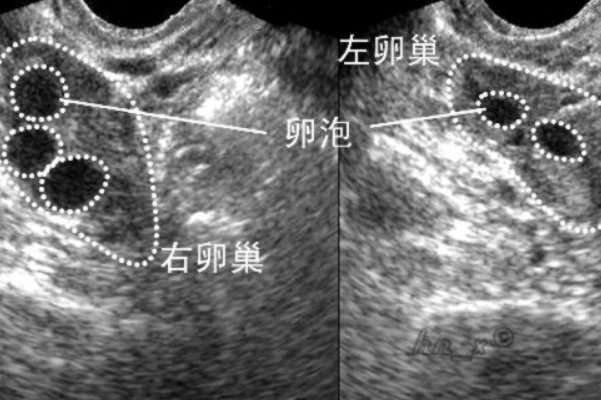

问题描述: 因为我的卵巢一直不太好,所以我就决定和丈夫去做了试管婴儿,上个周我去医院做了一个B超检查,主要是为了监测自己的卵泡的发育情况,当时医生跟我说,他并没有见到有优势的卵泡出现,所以让我回去再吃一段时间的促排药,但是我不太明白,没有优势卵泡是意味着有卵泡,但并不算优质,还是我的身体里就根本没有卵泡呢?

许多做试管婴儿的女性都会监测卵泡发育,对于某些卵巢功能不好的女性而言,她们在做B超检查的时候十分在意自己有没有卵泡,如果监测出没有优势卵泡,她们会非常疑惑,不明白到底自己有没有卵泡可以用,事实上,下面几种因素都会影响B超监测卵泡的结果:

1、技术问题:在进行B超检查时,操作者的技术水平和经验可能会影响结果的准确性。B超的操作需要一定的技巧和经验,包括选取合适的探头、调整仪器的参数等。如果操作者技术不熟练,可能无法准确地检测到优势卵泡,或者将其误认为其他结构。

2、卵巢功能问题:连续监测未见优势卵泡,存在卵泡发育不良或排卵障碍,会影响怀孕。原因可能是多囊卵巢综合征、卵巢功能低下、泌乳素高等,需要完善激素六项等检查并使用药物促排卵。因此,即使进行了B超检查,也可能无法见到优势卵泡的存在。

3、周期问题:卵泡的发育是一个周期性的过程,需要经历多个阶段才能形成成熟的卵泡。如果进行B超检查的时间点不恰当,可能会错过优势卵泡的发育阶段。因此,未能见到优势卵泡并不意味着完全没有卵泡的存在,而可能只是因为检查的时机不合适。